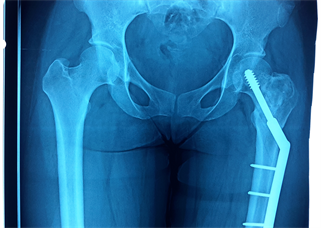

At six months postoperative, the patient was asymptomatic. A good fusion of the bone graft was noted (Figure 4).

Figure 4. X-ray at six months postoperative showing good fusion of the bone graft.